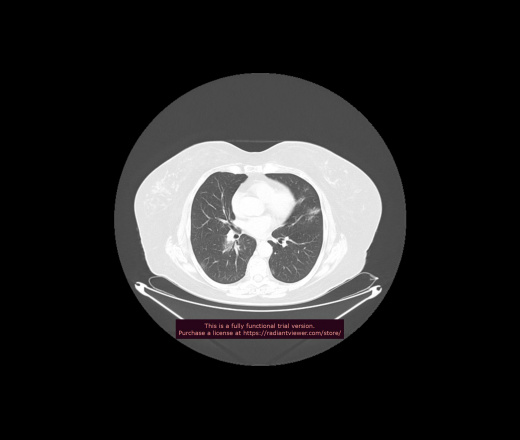

Уважаемые коллеги, если имеется интерес, сможете ли Вы спрогнозировать дальнейшее +-одинаковое течение процесса у 4 данных разных пациентов? Зацепиться где-то можно очень просто, где-то нельзя.